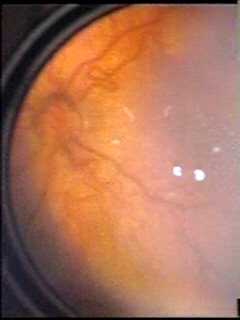

O objetivo do atendimento sistemático aos nascidos no grupo de risco é determinar o momento adequado para o tratamento que, nos dias de hoje, ainda é eminentemente cirúrgico podendo ser feito tanto pela crioterapia quanto pela fotocoagulação por laser. O tratamento previne o descolamento da retina e está indicado quando as complicações da isquemia e da neovascularização se fazem presente na periferia (quase sempre no setor temporal) associado à chamada doença plus que é caracterizada por um aumento anormal do calibre vascular venoso ou mesmo arteriolar em toda a retina (Figura 2).

Figura 2. Imagens de fundo de olho de RN pré-termos mostrando dilatação e irregularidades vasculares na retina conhecidas como “doença plus”.